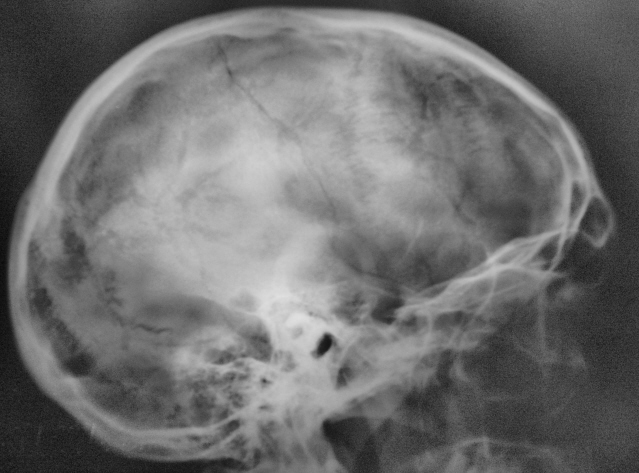

Пациент в ургентном порядке, после ДТП был доставлен в ЦРБ в ночное время. Был вызван "ургентный лаборант" для рентгенографии черепа. Пациент без сознания. С учетом состояния пациента рентгенография произведена в нестандартных проекциях - "задняя прямая".

Линейный перелом костей крыши черепа, возможно с переходом на основание. Вот только не понятно есть или нет импрессионный перелом височной кости, а ещё больше похоже на наличие пневмоцефалии.

А что скажите по поводу пирамидки и орбиты справа?

Контуры пирамиды чёткие, а вот латеральная стенка орбиты возможно сломана. Он был отправлен в ОКБ?

Линейный перелом с переходом на основание - дно средней черепной ямки. Сейчас вопрос о пирамидке и орбите не принципиальный. Главный вопрос нет ли внутричерпной гематомы. Если больной выйдет из тяжелого состояние, и встанут экспертные вопросы можно сделать Стенверс при потере слуха, Майер при кровотечении из уха. Насчет стенки орбиты - наличие перелома сомнительно, явно не видно. Также можно доснять при улучшении состояния. Судя по всему это молодой человек. Сколько лет?

Вижу только линию перелома височной и теменной костей, высока вероятность перехода на основание, остальное - домыслы и сомнения.